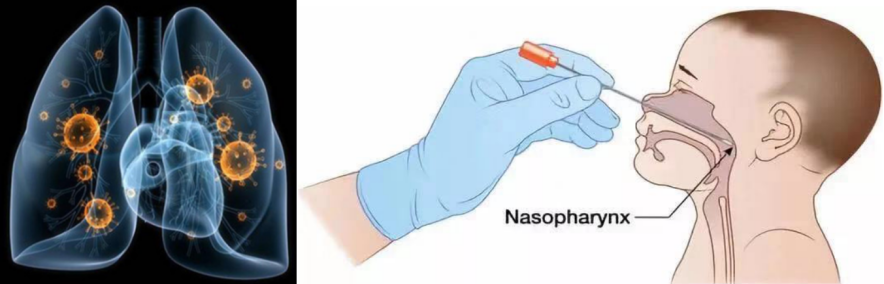

咳嗽,喷嚏,是人体呼吸道最常见的保护性防御性反应,一是为了阻止外面异物进入气道or肺内部,二是为了排出气道or肺内部垃圾到体外。 空气中化学物质(烟雾、甲醛、一氧化碳、二氧化硫...) or 颗粒物质(PM2.5、PM10、植物花粉、宠物皮屑...)or微生物(尘螨、霉菌、细菌、病毒...),是婴幼儿咳嗽最常见诱因 !

2. 病理性咳嗽 是呼吸道感染 or 过敏 or 异物等诱发的咳嗽,是炎症性咳嗽 or 刺激性咳嗽:咳嗽频繁 or 咳嗽持续 or 咳嗽影响孩子吃拉玩睡(不吃、不玩、精神萎靡、睡眠不安)or 咳嗽伴呼吸困难 【 鼻煽( 鼻孔大小随呼吸变化 )、喘鸣( 呼气时有哮鸣声音 )、气促( 2个月内婴儿每分钟呼吸≧60次;1岁内婴儿每分钟呼吸≧50次 ;5岁内儿童每分钟呼吸≧40次 )、青紫( 唇周颜色发紫 )、吸凹( 吸气时锁骨上下胸骨上下肋骨上下有明显凹陷 ) 】 or 咳嗽伴有其他症状(头痛、耳痛、胸痛、发热、呕吐...)。孩子病理性咳嗽,需要看医生,寻找病因,治疗处理 !